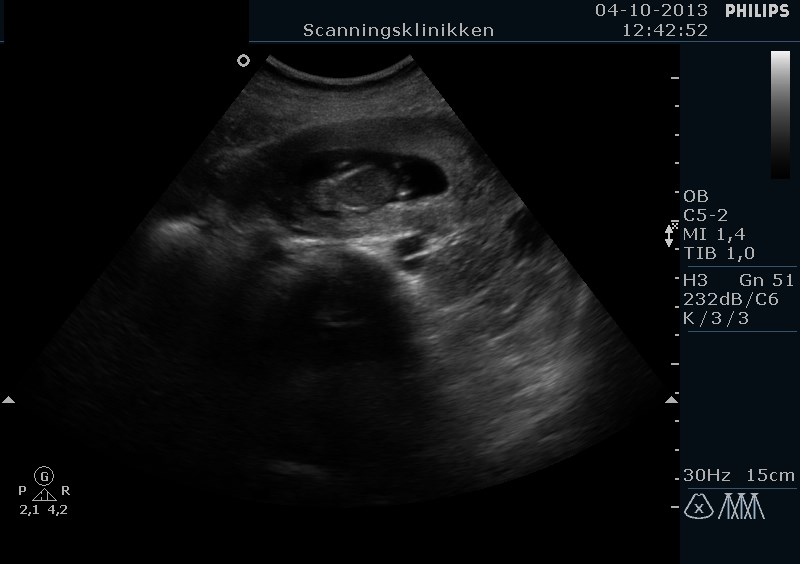

Men se lige hvad vi har set i dag. En lille spire på næsten 5 cm og er 11+5 uger henne med en termin den 20 April <3